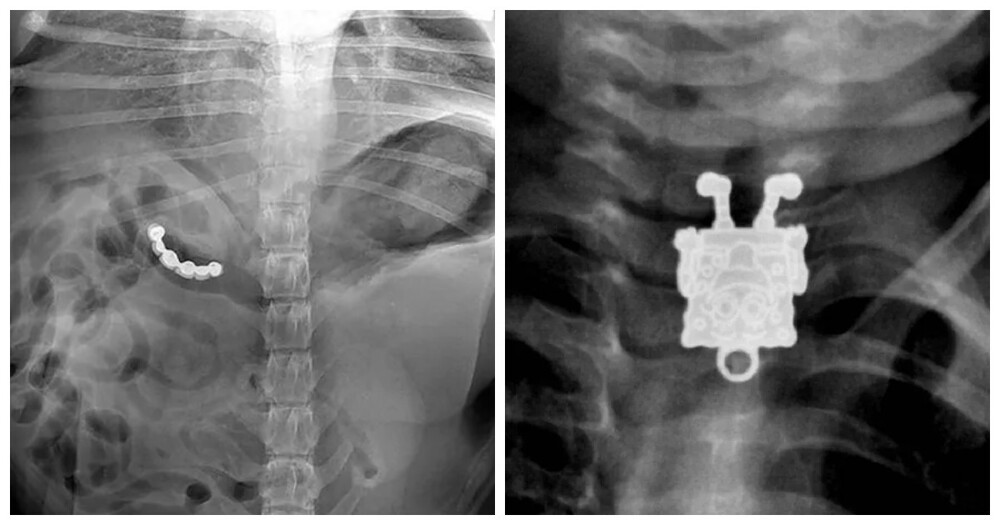

У них це було в тілі: 17 дивовижних рентгенівських знімків (18 фото)

Лікарі-рентгенологи та хірурги за свою багаторічну практику бачать багато чого дивовижного та несподіваного.

10. Англійська шпилька